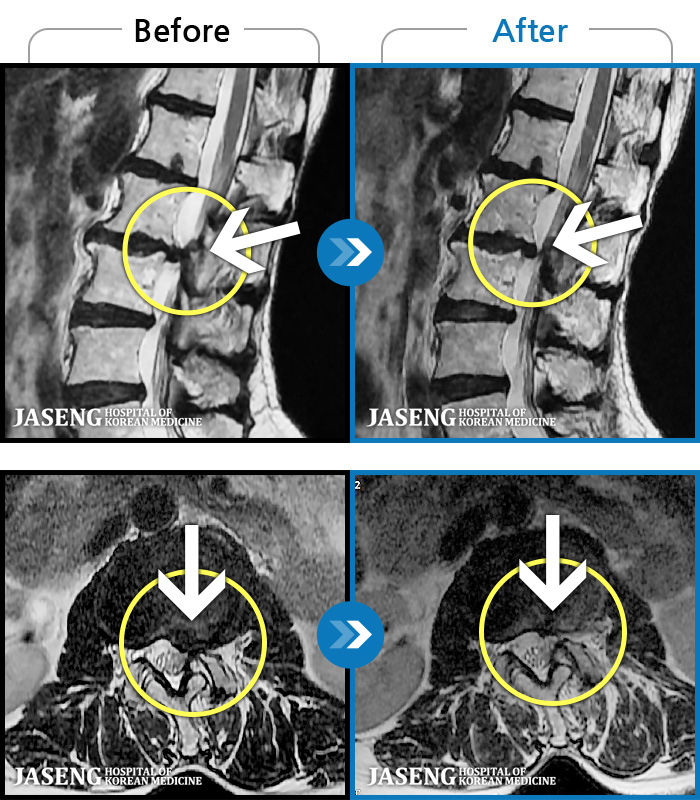

김상돈 원장님 칭찬 드립니다 대학병원,척주질환 전문 병원에서 목디스크 수술 진단을 받았었는데 지인 추천으로 자생한방병원을 방문 했었는데 김상돈 원장님께서 친절한 설명과 성심성의 치료를 해주신 덕분에 일상 생활을 정상 적으로 하고 있습니다 원장님 감사합니다